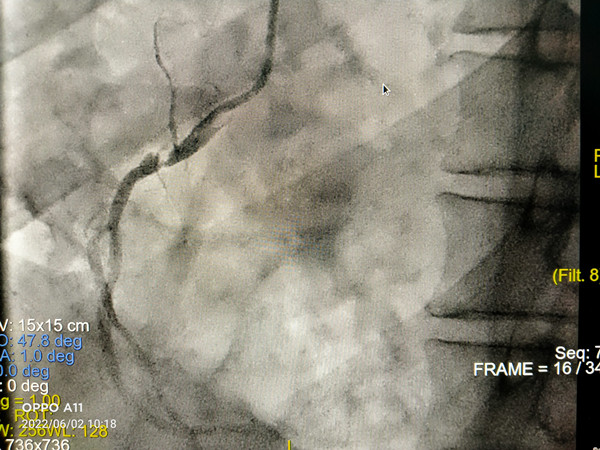

在我院心外科裴斐主任医师,麻醉科刘鹏斌主任医师、罗斌主治医师,超声科韩东刚副主任医师、金鑫主治医师,曹春晖护士长领导的护理团队等多学科协助下,韩振华主任、王新宏副主任医师、刘小军主治医师等先为患者行冠脉造影提示右冠近段95%狭窄(图1),先行PCI干预,右冠植入3.0x22mm支架1枚(图2)。后成功为患者植入TAV24mm VitaFlow瓣膜系统,DSA造影显示主动脉瓣位置良好,未见明显瓣周漏(图3),左右冠脉造影正常,术后即刻心脏超声示最大跨瓣流速129cm/s,最大跨瓣压差7mmHg(图4),顺利结束手术。